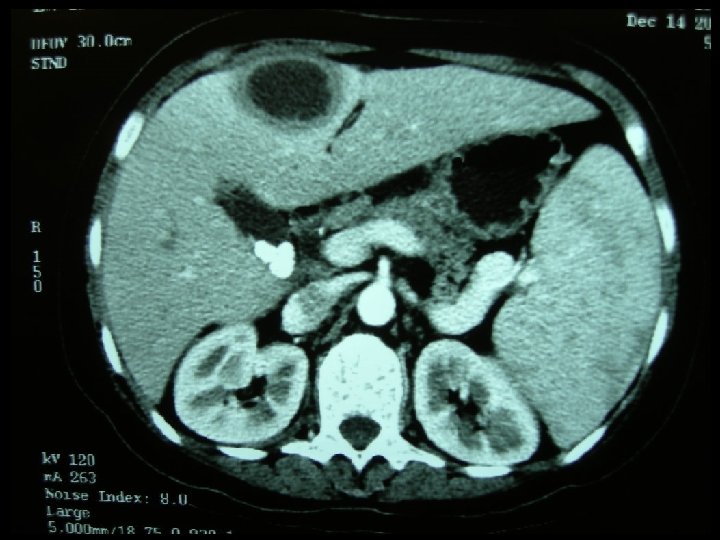

Question 4 • A 34 -year-old woman complained right upper quadrant pain and fever for five days. Mild localised tenderness was elicited at the right upper quadrant. She was not pregnant. BP was 109/61 mm. Hg and pulse rate was 102/min. (a) Suggest 4 differential diagnoses. (b) List 3 abnormalities of the CT film.

Answer 4 (a) Biliary colic, acute cholecystitis, acute cholangitis, hepatitis, liver abscess, RLL pneumonia (b) CT: multiple gallstones; complicated cystic lesion (infected cyst or abscess), hepatosplenomegaly

Question 4 (c) What is the most likely diagnosis? Liver abscess (d) Give 2 possible causative organisms of this disease in (i) Developed: E. Coli (most common), K. pneumoniae, Bacteroides, Enterococci, Anaerobeic Streptococci, and Microaerophilic Streptococci (ii) Developing: Entamoeba histolytica